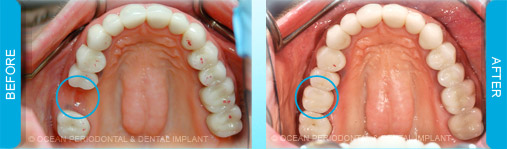

Dental implants are commonly used to replace missing or lost teeth in order to ensure patient comfort, function, and aesthetics. Indeed, there are many treatment options for management of missing teeth, such as bridges, and partial/complete dentures.

Nonetheless, numerous studies have demonstrated that implant-supported restorations are generally deemed to have superior functional and aesthetic outcomes. Furthermore, there are cases where dental implants may be the only logical choice for the restoration of function and aesthetics.